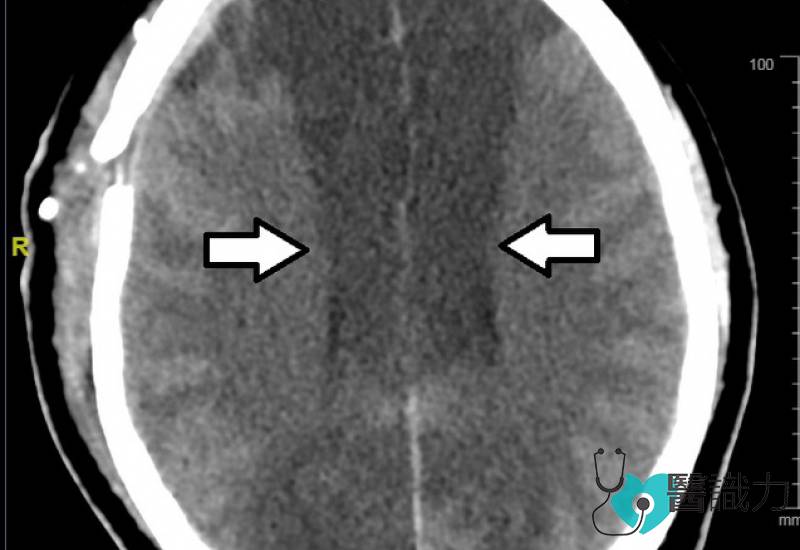

左图:脑动脉破裂导致蛛网膜下腔出血;右图:严重血管痉挛(vasospasm)导致缺血性中风。

脑部断层扫描显示,阿末的珠网膜下腔出血,严重的出血性中风造成激烈头痛和突然昏厥。以中风病人来说,42岁的阿末属于年轻病人,造成年轻病人出血性中风的原因离不开动脉瘤血管爆裂。

但天不如人愿,术后第三天可怕的后遗症爆发了──虽然事前做足了防范措施,但阿末依然出现严重的血管痉挛(vasospasm),引发术后缺血性中风。由于发生痉挛的是主要的脑血管,受影响的范围很广,很快地阿末的瞳孔开始放大,脑下垂体严重缺氧,体内各器官也开始失调,盐分滞留体内,血钠节节高升,导致癫痫和脑肿。

严重的珠网膜下腔出血病人可能在手术后面对各种后遗症,包括脑周围血管收缩而导致血管痉挛(vasospasm),引发术后缺血性中风。病人越年轻,发生术后缺血性中风的几率越高。没有做手术的珠网膜下腔出血病人,也可能因周围血块发炎而导致血管痉挛,引发缺血性中风。